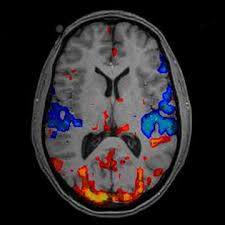

有一种叫(fMRI,functional magnetic resonance imaging,功能核磁共振成像)的技术,常被用来研究大脑活动,下面贴了几张大脑成像: